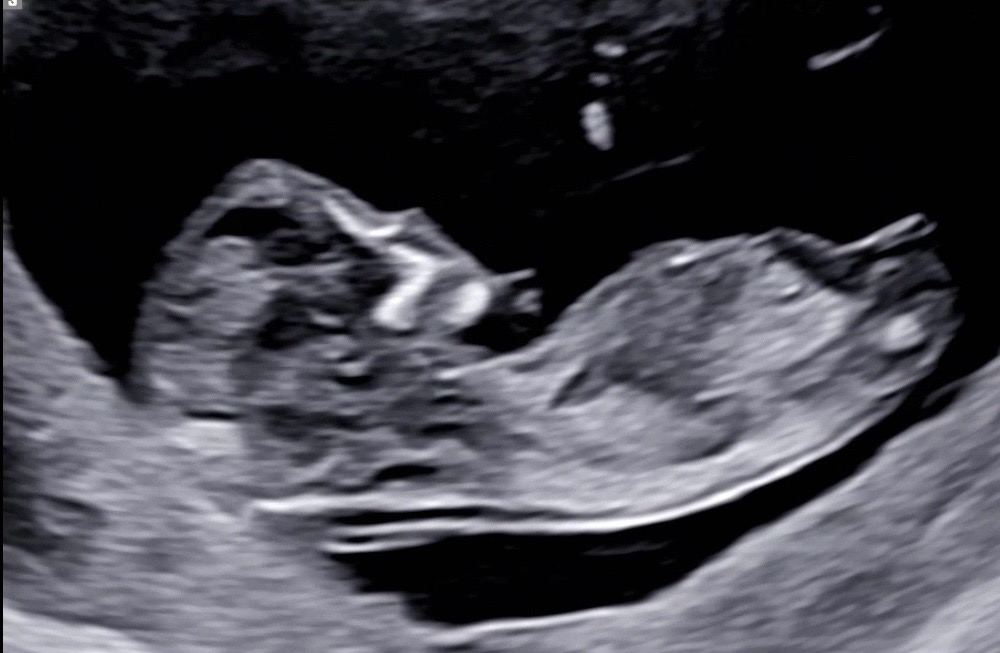

11주 6일 각도 어때보이나요?☺️

각도가 애매한 것 같은데 아들 각도일까요 딸 각도일까요??😂😂